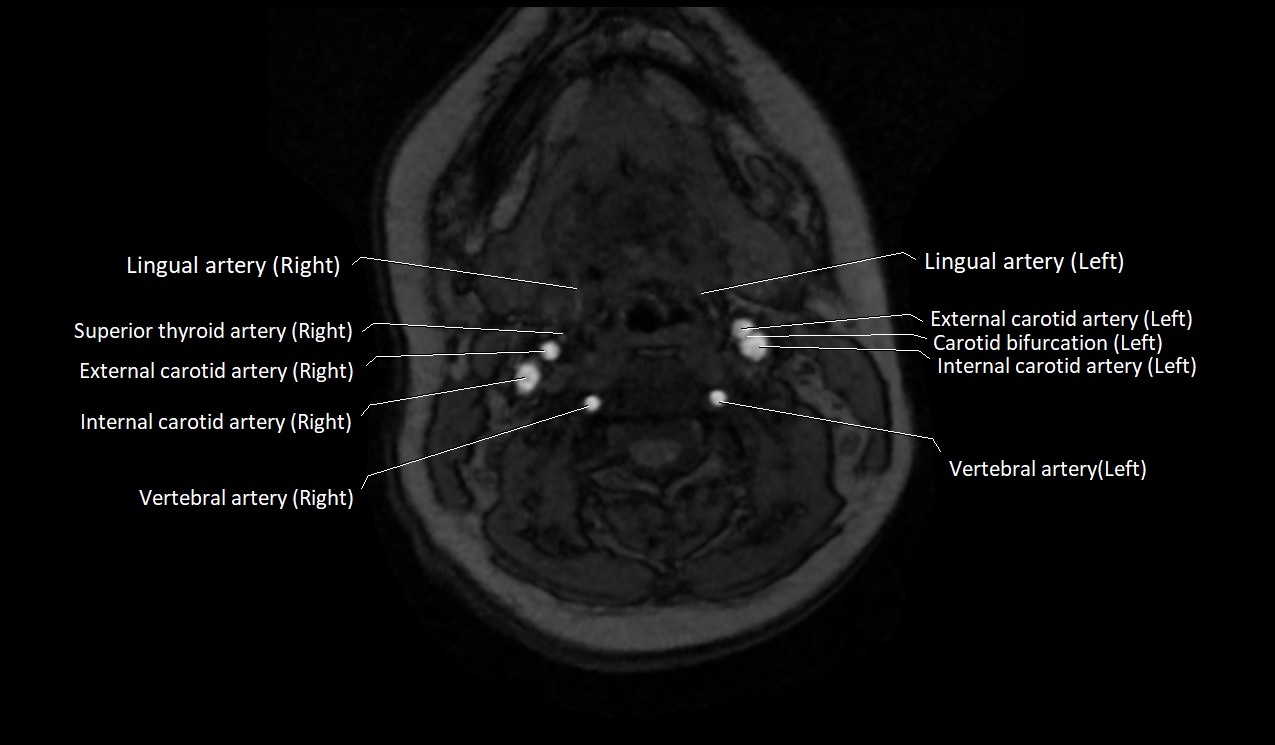

CT Appearance:

• Appears as a small, thin-walled, contrast-enhancing vein in the anterior neck

• Best visualized in the lower neck just lateral to the midline

• Non-contrast CT: difficult to differentiate from surrounding soft tissue, may appear as a hypoattenuating tubular structure